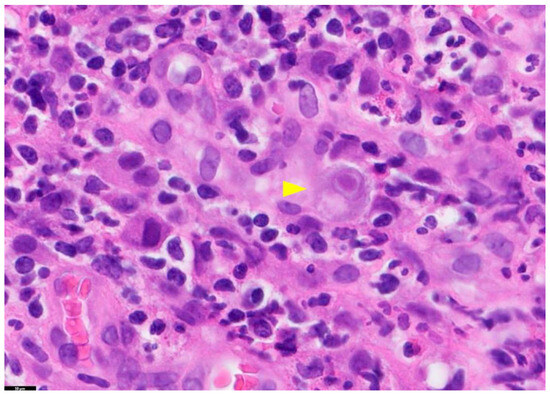

The gold standard for diagnosing tissue-invasive CMV disease is a histologic examination of biopsy samples [17]. This method involves identifying enlarged cells and nuclei and detecting the presence of intracellular viral inclusions, usually basophilic intranuclear inclusions (called megaloblasts), although eosinophilic cytoplasmic inclusions may also be observed [16,17] (Figure 1). The diagnosis of CMV infection in tissue sections can also be established by immunohistochemical staining or in situ hybridization methods [16]. However, due to the invasive nature of the procedures involved in histopathology, routine CMV testing of liver transplant donors is not recommended.

Figure 1.

Tissue Section of a CMV-Positive Cell. This figure presents a tissue section of a CMV-positive cell, specifically illustrating CMV gastritis. The yellow arrow in this image highlights a cytomegalic cell with a basophilic intranuclear inclusion encircled by a halo. The staining method used is Hematoxylin and Eosin (H&E), and the magnification is 100×. PathologyOutlines.com, a reputable pathology resource platform, provides the figure. Copyright for this figure is attributed to the original authors.